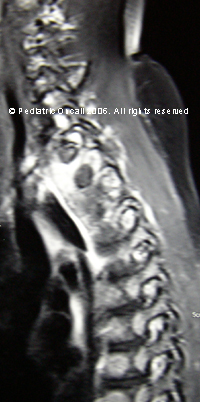

Intraspinal tumor

This child presented with acute onset paraplegia.

What is the diagnosis?

Intraspinal tumor. Commonest intraspinal tumors in children include astrocytomas, neuroblastomas, sarcomas, ependymomas and neurofibromas